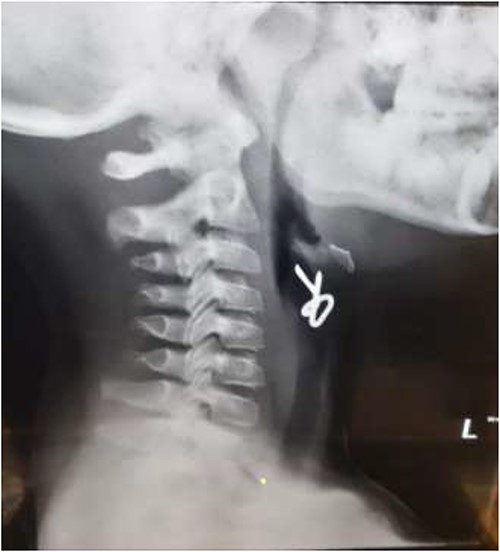

The first case is of a 7-year-old child presenting with a history of barbed wire inhalation. X-ray imaging of his neck and chest showed a radio-opaque object visible in the upper airway with sharp edges (Figs 1 and 2). Due to the position of the foreign body, endotracheal intubation was not feasible. A trial of apnoeic oxygenation using high-flow nasal oxygenation was used as an alternative, and this allowed for an unobstructed view of the larynx, facilitating the safe removal of the foreign body (Fig. 3).

Lateral neck X-ray showing a radio-opaque object with sharp edges visible.